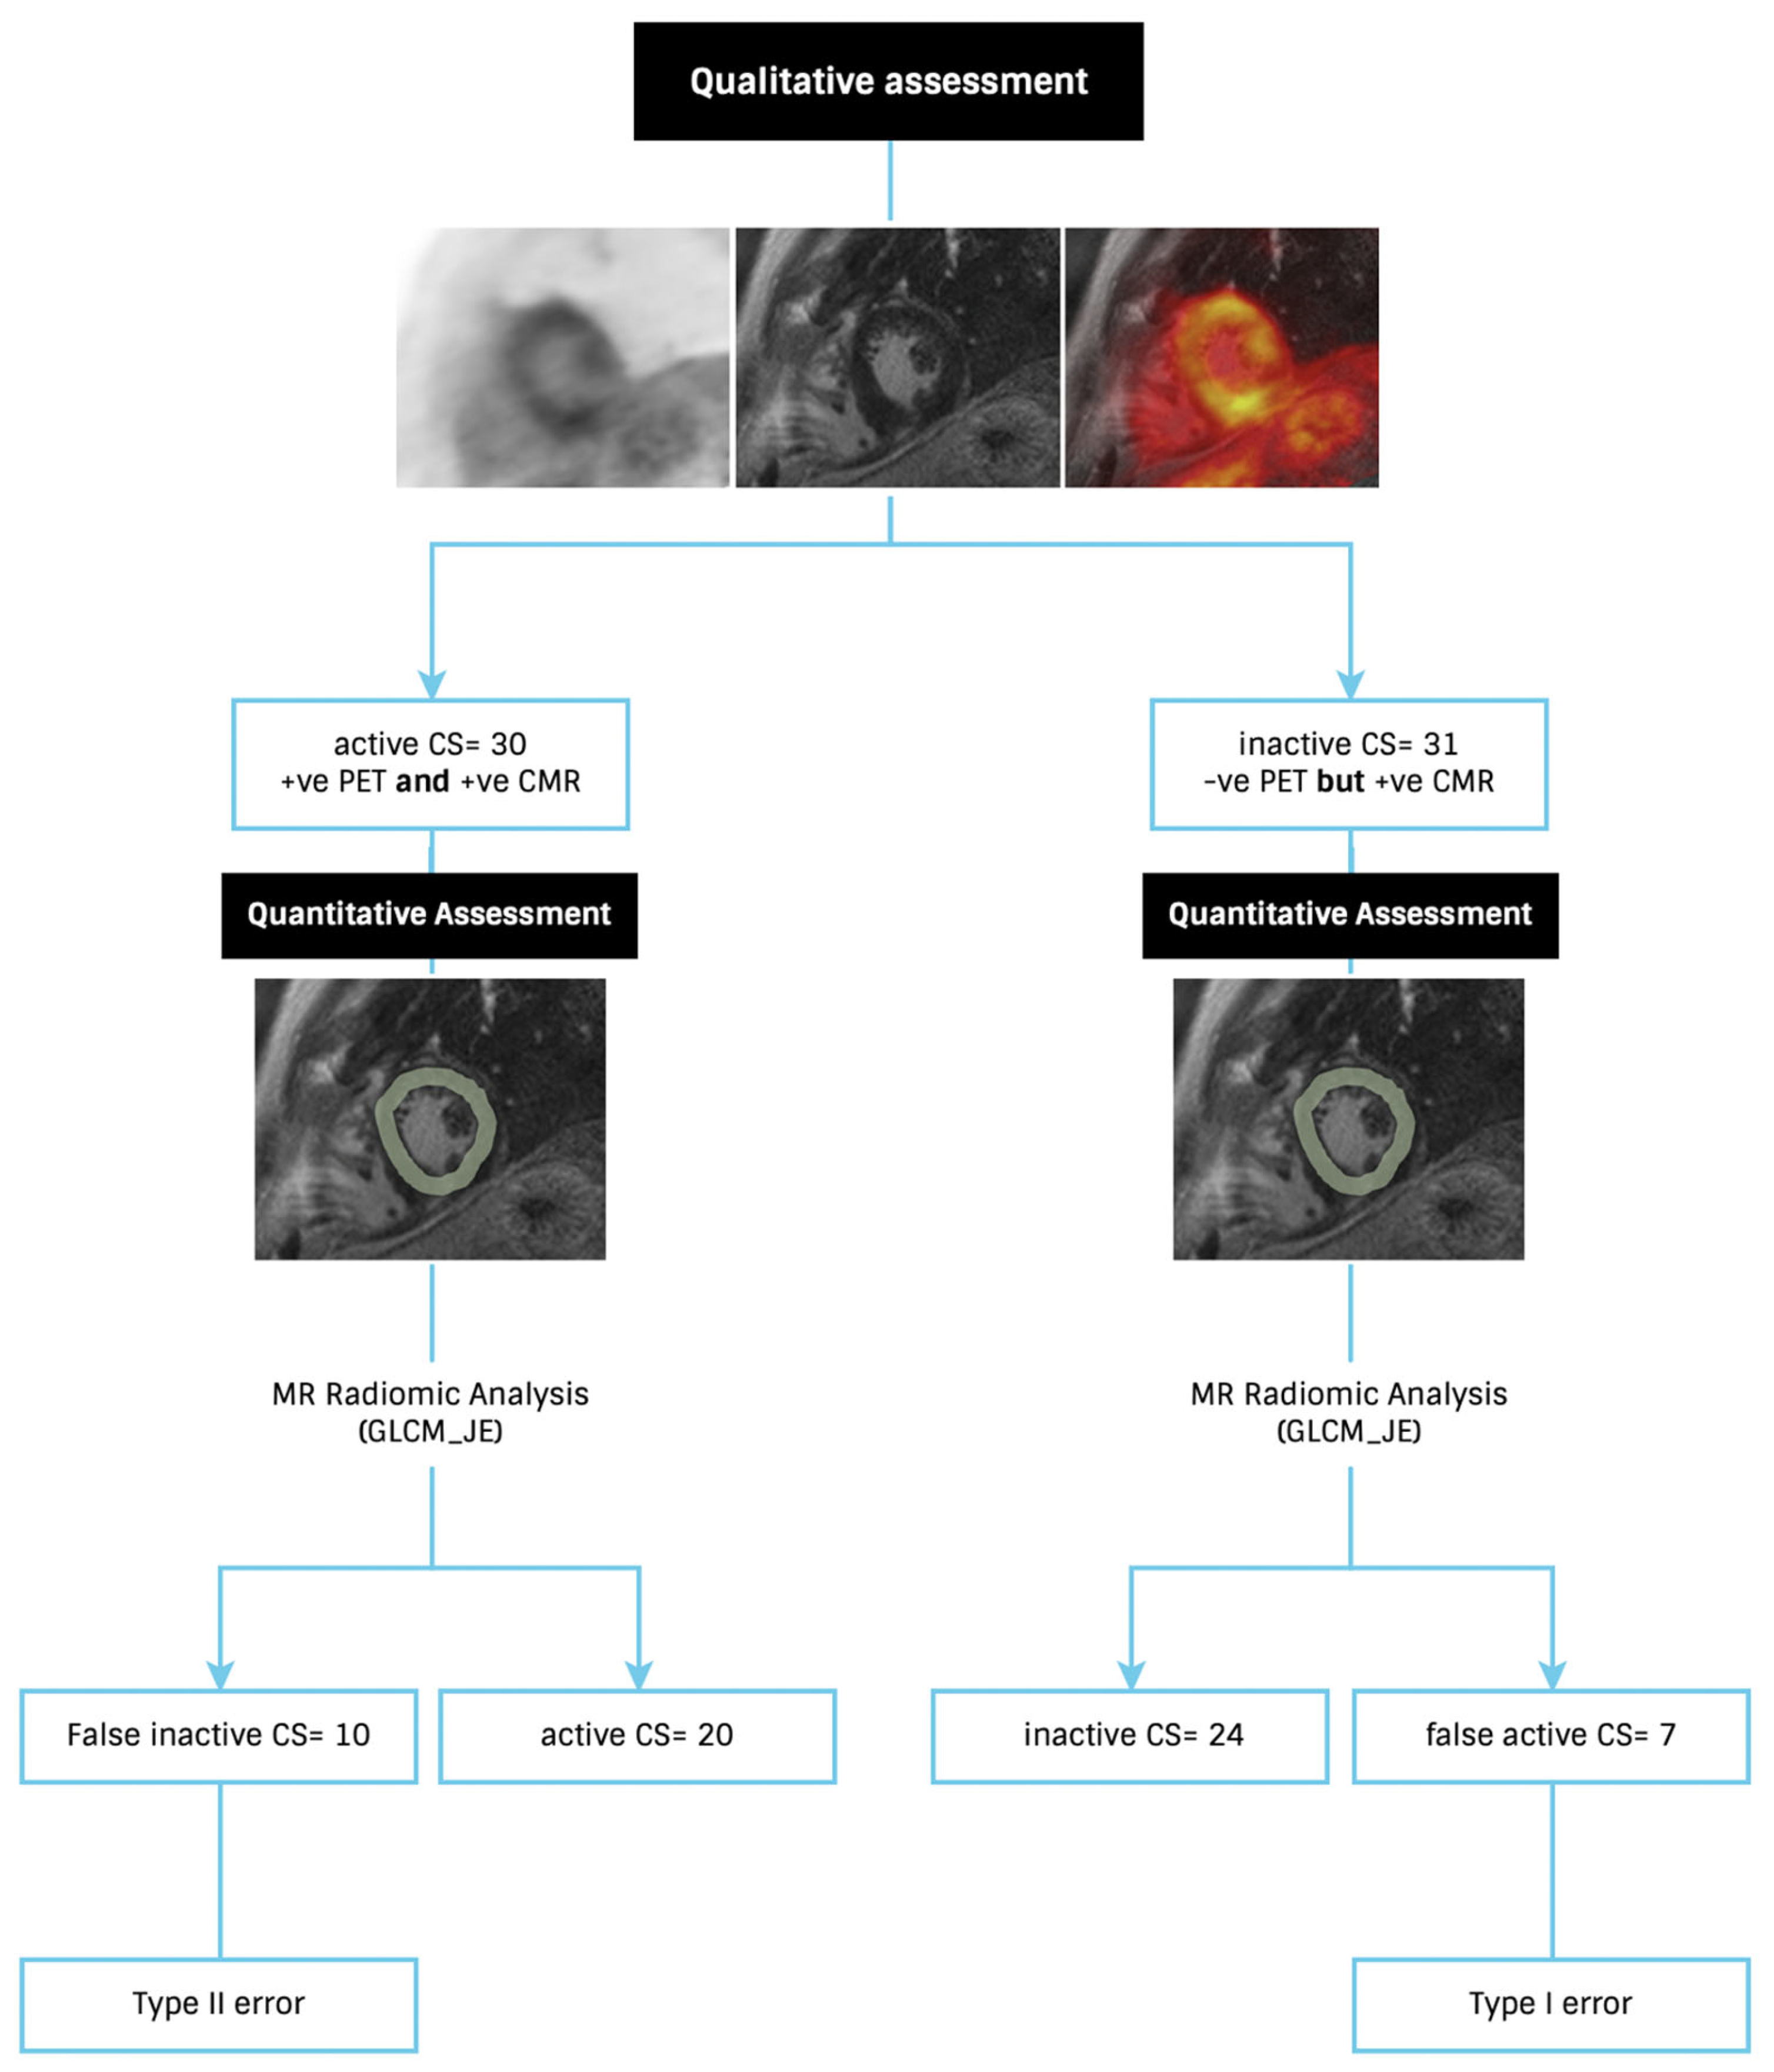

3.1. Individual Features—Diagnostic Utility

3.2. Signature Building and Machine Learning Performance

4. Discussion